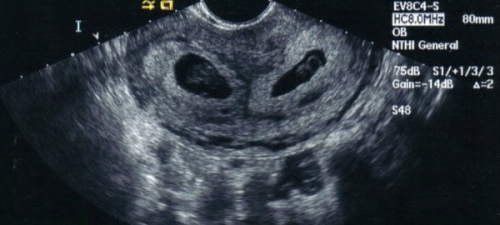

Беременность двойней после ЭКО обладает особыми симптомами и признаками. Один из методов, позволяющих не только выявить многоплодную беременность, но и оценить ее прогресс, заключается в определении уровня ХГЧ (хорионического гонадотропина) – гормона, который вырабатывается тканями хориона после имплантации эмбриона.

ХГЧ при двойне после ЭКО служит индикатором для различения одноплодной и многоплодной беременности. Врачи ориентируются на значения этого гормона и его динамику за определенные временные промежутки. Специальная таблица ХГЧ по дням после ЭКО и для беременности двойней была разработана медицинскими специалистами: